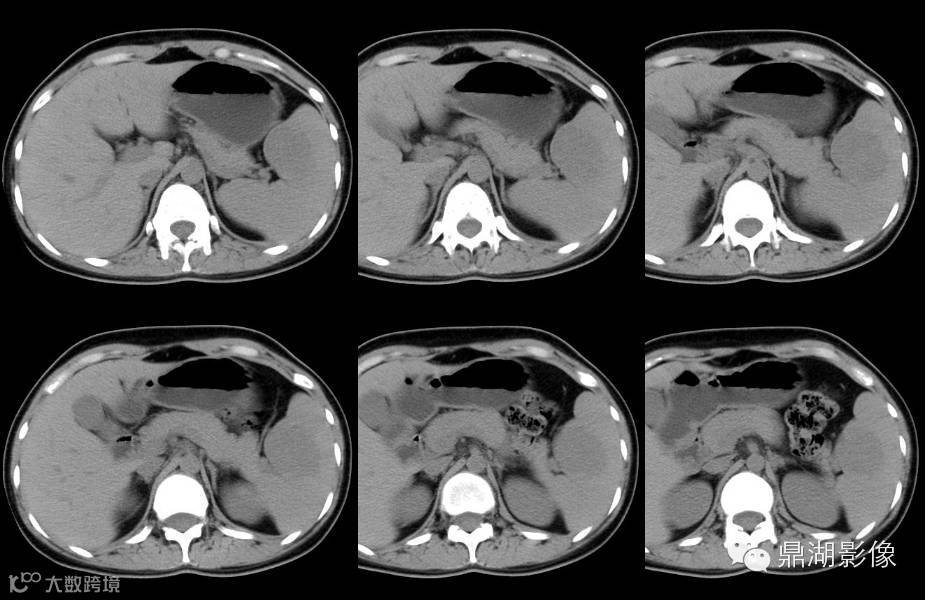

女,19岁,左上腹痛一周,查体无发热,体重为减轻,全腹未见腹部包块。以下为其CT平扫及增强扫描。

平扫

增强扫描特点:动脉期肿块边缘点状及线条样强化,门脉期及延迟期强化渐向中部充填,与脾脏几成等密度,肿块显示渐缩小。是不是让你觉得很简单,但是答案是: